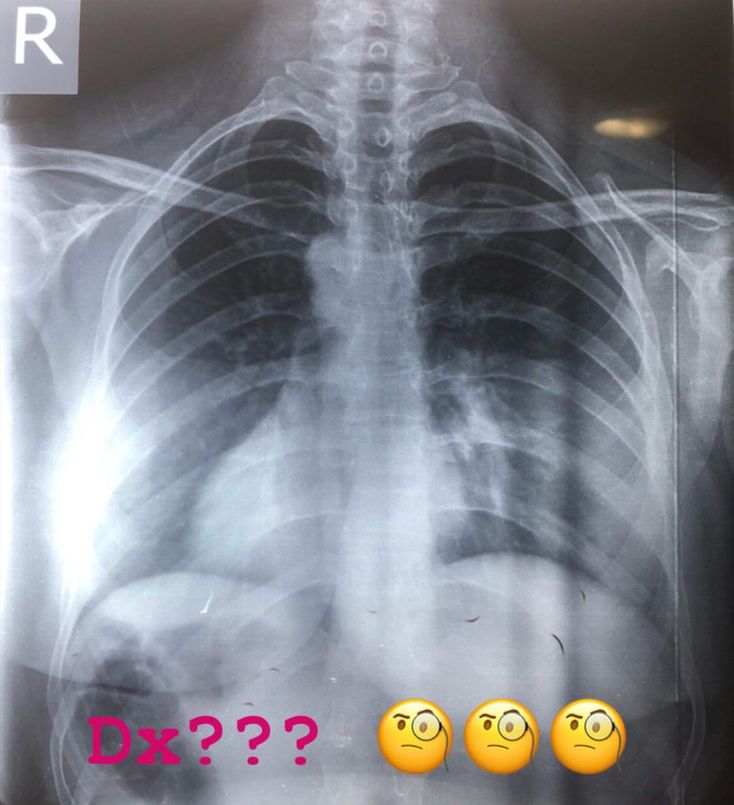

Look well to the x-ray and then tell me about your diagnosis

it is not just dextrocardia.......but it seems to be a case of situs inversus.......look at the gas shadow present below the diaphragm on the right (may be an indication of fundal gas shadow)

nice answer but Not only dextrocardia ... the case is situs inversus totalis.. can see the liver in the left side